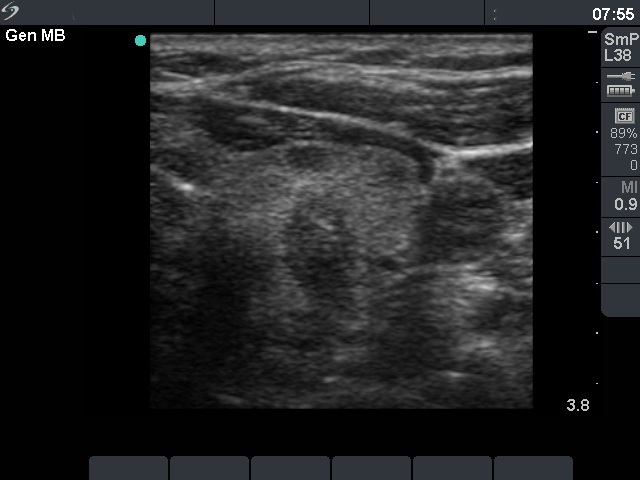

Characteristic ultrasound properties - irregular borders of the nodule

The borders of a papillary carcinoma is frequently irregular, lobulated.